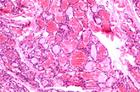

鼻咽部纖維血管瘤為鼻咽部常見的良性腫瘤,好發於10-25歲男性青少年。病理上腫瘤由有纖維組織基質包繞的形狀和大小各異的血管間隙組成。

病因尚不明確,可能與性激素、發育異常、炎症刺激等因素有關。本病起源於鼻咽頂部的纖維組織及血管組織,多為圓形、橢圓形,基底廣或有蒂,瘤體深紅或灰紅色,表面光滑,有類似鼻黏膜的上皮覆蓋,但無包膜,上皮下可見明顯擴張的血管,血管壁薄,為單層上皮,其下為平滑肌,缺乏彈性組織,不易收縮,易大出血。組織學上雖屬良性,但由於腫瘤逐步增大,可壓迫鄰近骨壁,侵入鼻竇、眼眶、翼齶窩,甚至破壞顱底而造成嚴重後果